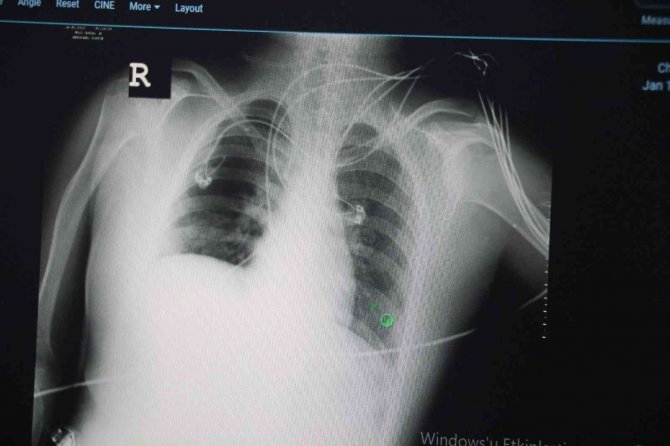

Son olarak varyantların akciğer tutulumları hakkında da bilgiler veren Dikmen, şunları söyledi:

"Delta varyantına yakalanan hastalarda akciğer tutulumunun daha fazla olduğunu görüyoruz. Omicron varyantına yakalanmış bir hastanın akciğer filmine baktığımızda ise deltaya göre çok az kaldığını görebiliyoruz. Bu da omicron geçiren bir hastanın, delta varyantına yakalanan bir hastaya göre daha rahat nefes aldığını gösteren bir durumdur."